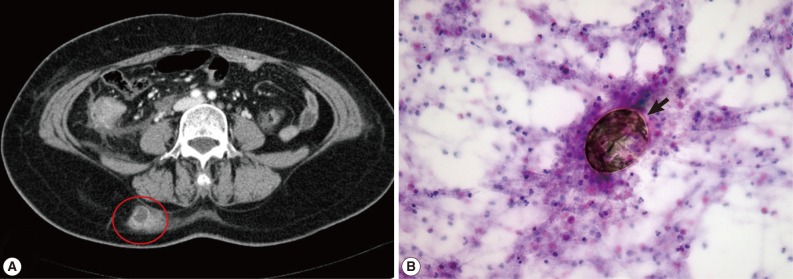

A 58-year-old woman visited our hospital for evaluation and treatment of the right flank pain over 4 days (August, lived in Namwon, Jeollabuk-do). Her vital sign was stable and physical examination revealed no specific signs. Laboratory findings showed no abnormalities, except eosinophilia (14.6%). Abdominal CT revealed localized abscess in the subcutaneous layer of the right back (

Fig. 2A). Fine needle aspiration cytology (FNAC) showed the eggs of

P. westermani with eosinophil-dominant inflammatory cells (

Fig. 2B). ELISA (performed at Seoul Medical Institute) was positive for antibodies against

P. westermani in the serum (0.69). Retrospective history results revealed that she had frequently consumed 'Kejang', which was prepared using freshwater crabs. On the basis of these findings, she was treated with praziquantel (25 mg/kg, 3 times daily for 2 days) and her right flank pain was resolved after treatment.

Fig. 2CT and microscopic findings of subcutaneous paragonimiasis. (A) CT scan shows localized abscess in the right back (red circle). (B) Fine needle aspiration cytology showed eggs of P. westermani (arrow) with eosinophil-dominant inflammatory cells. The eggs of P. westermani were yellowish-brown, ovoid or elongate, with a thick shell, and often asymmetrical with one end slightly flattened. H&E stain, ×400.